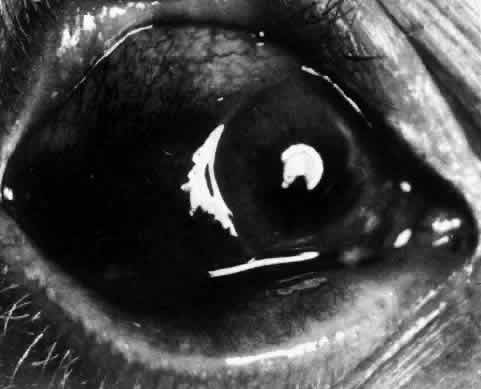

The inflammation of the eye is a prominent feature. The inflammation has a bluish-red hue in contrast to the brighter red of episcleritis and may be sectorial or diffuse. The severity of inflammation seems to depend on the amount of episcleral tissue present. Therefore, it is more prominent in younger people and is least prominent in those with rheumatoid arthritis in whom the episcleral tissue almost disappears. Each of the various types of scleritis can be distinguished by its typical clinical appearance. Because the pathologic change is in the sclera, there is always edema and/or necrosis of that tissue. This gives rise to an overlying episcleral edema and to congestion that may be very severe and may need blanching with epinephrine 1:1000 or phenylephrine 10% to detect the underlying edema. The sclera that is edematous is pushed forward, and the deep episcleral network is more congested than the superficial networks (Figs. 27 and 28). It is usually easy to ascertain by simple observation that the patient has scleritis and not episcleritis. However, it is not as easy to ascertain whether the patient has early necrotizing scleritis. It is in these patients that fluorescein angiography has considerable value, because the first changes are detectable in the ocular vasculature. Prompt and adequate treatment can prevent these changes from becoming irreversible.

Diffuse Anterior Scleritis Diffuse anterior scleritis is the most common and least severe type of scleritis. The inflammation is widespread, and it may involve either a small segment or the whole of the anterior segment, sometimes with such severe overlying inflammation as to justify the name “brawny” scleritis (Fig. 29). On slit lamp examination, the vascular pattern of both deep and superficial layers may be distorted, so that the normal radial pattern of the vessels is lost; large anastomotic channels develop, leading to beading and tortuosity of the remaining vessels (Figs. 30 and 31; Color Plate 1C).

Nodular Anterior Scleritis Although patients with nodular anterior scleritis resemble those with nodular episcleritis on cursory examination, detailed examination reveals marked differences. The nodule or nodules (they may be multiple) consist of scleral tissue that is immovable episclera is tightly adherent to the nodule, which is tender to the touch. Although the sclera sometimes becomes transparent below the nodule, it does not become necrotic, nor does the condition extend beyond the site of the nodule, as occurs in necrotizing scleral disease (Fig. 36). (see Fig. 28; Figs. 34 and 35). The edematous